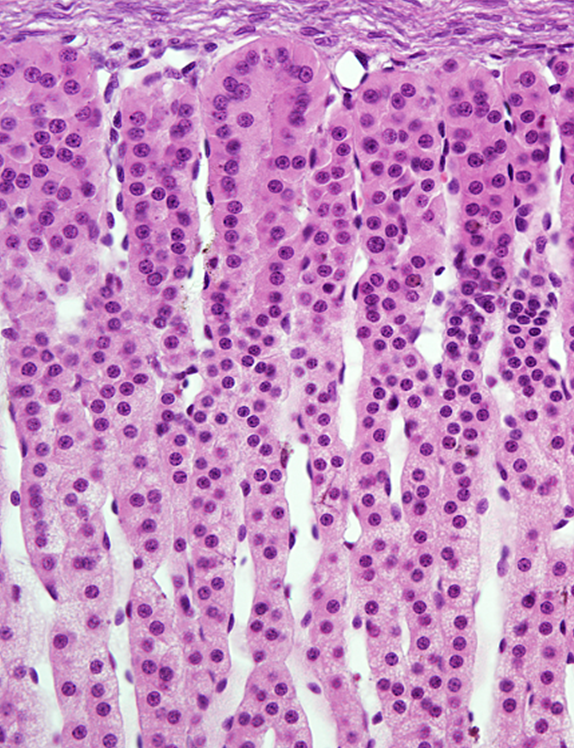

Epidídimo - Epitélio pseudo estratificado

Trompa uterina

1: Trompa uterina - mucosa